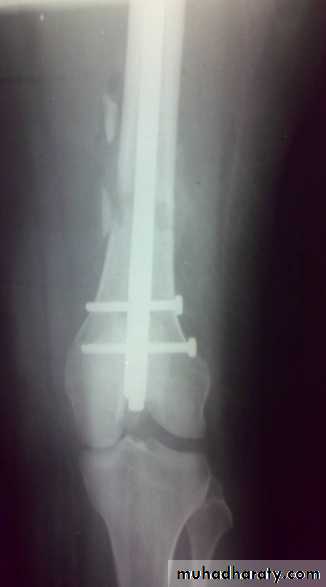

Intramedullary nail with interlocking screws is the method of choice

External fixation

Indications:Open injuries.

Multiple injuries to reduce operating time.

Bone transport for bone loss.

In adolescents.